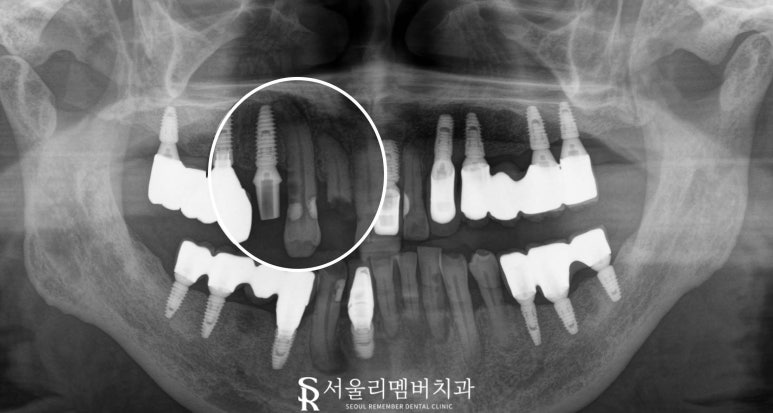

구강을 살펴보니,

오른쪽 위 두 번째 측절치는 파절(부러짐),

옆 송곳니는 심한 충치가 있었습니다.

특히 송곳니의 충치는

치근(치아 뿌리)까지 이어져 있어

조만간 극심한 통증이 발생할 것으로 예상됩니다.

또한 첫 번째 작은 어금니는

이전에 임플란트 시술을 받았으나,

위쪽의 크라운 보철물이 떨어진 상황이었습니다.